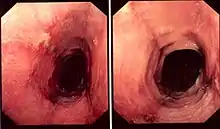

While the diagnosis of lymphocytic esophagitis depends on the biopsy results, certain changes can be visualized directly at the time of endoscopy. The esophagus may be narrow in calibre,[5] may show multiple rings,[5] redness,[5] linear furrows[1] or the mucosal lining may slide demonstrating a "crepe-paper" appearance.[1] Complications such as strictures of the esophagus can also be detected with endoscopy.[5] These changes are very similar to those found in eosinophilic esophagitis, a more common and better understood esophageal disorder thought to be of allergic origin.[5] Narrow-band imaging with magnification endoscopy is another imaging modality that can show characteristic changes of lymphocytic esophagitis.[7]